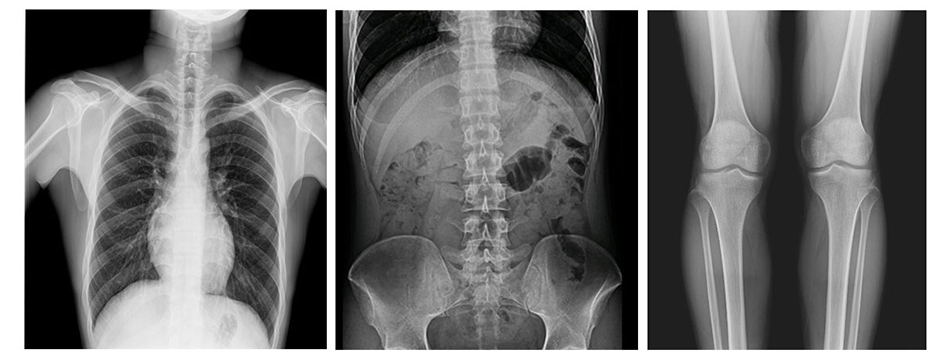

5、自動圖像拼接功能(選配)

應用于全脊柱、全下肢的檢查,為臨床提供高精度的全景圖像。完全滿足醫院的骨科及矯形手術要求。